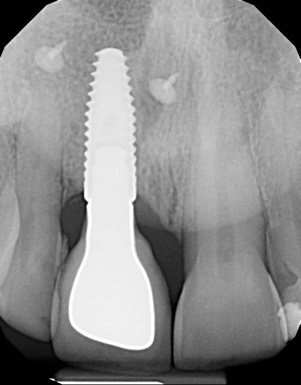

The digital wax up allowed the implant position to be planned based on the ideal prosthetic position of the final restoration (Figure 14). The planned implant position adhered to the aforementioned guidelines for ideal implant placement regarding the buccal, interproximal, and apical bone, and its platform would be located 4-mm apical to the planned restorative margin. In the coronal plane, the implant was centered with the gingival zenith in a position that was located approximately 1-mm distal to the midline of the edentulous space. Following implant planning, a tooth-supported surgical guide was designed and then 3D-printed to facilitate fully guided surgical implant placement.

Prior to the initiation of the surgery, the surgical guide was tried in to confirm proper seating and stability (Figure 15). A flapless approach was not considered because the need for further bone grafting at the time of implant placement had been anticipated through the digital planning. A slightly palatal crestal incision was made, followed by two vertical incisions on the mesial and distal aspects of the edentulous site in order to preserve the papilla and avoid additional esthetic compromise to the anterior sextant. Next, a full-thickness flap was elevated to facilitate removal of the tenting screw and permit visualization of the buccal plate (Figure 16). A standard guided protocol was followed to place the implant, and its final position mirrored that of the digital plan. As predicted, the prosthetically driven implant position resulted in an insufficient buccal plate (Figure 17); therefore, additional guided bone regeneration was performed to reinforce the area and prevent future breakdown (Figure 18 and Figure 19). Making periosteal incisions could have compromised the blood supply to the flap, so instead, it was stretched in order to achieve tension free coronal advancement.31The flap was secured utilizing horizontal mattress sutures with additional supportive interrupted sutures to ensure primary closure (Figure 20). An immediate postoperative periapical radiograph (Figure 21) and CBCT scan (Figure 22) were taken, demonstrating a final implant position centered with the planned location of the gingival zenith.

(14.) Three-dimensional implant treatment planning.

Figure 14

(17.) Implant placed 1-mm distal to the midline of the edentulous space, corresponding with the planned location of the gingival zenith. Note the lack of sufficient bone buccal to the implant that necessitated further grafting.

Figure 17

(21.) Postoperative periapical radiograph taken immediately after placement of the implant at site No. 8 demonstrating implant positioning centered with the planned location of the gingival zenith and two titanium alloy tacks that were used to stabilize the resorbable membrane apically.

Figure 21

(22.) Immediate postoperative CBCT scan.

Figure 22